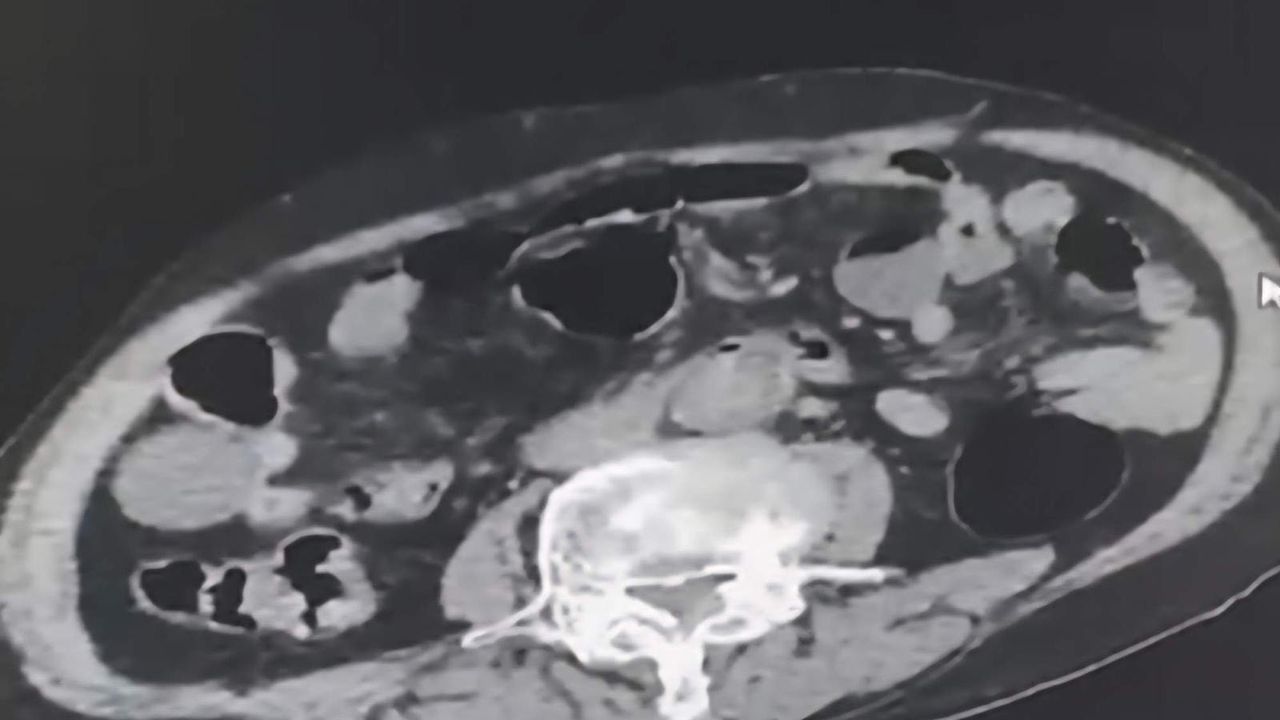

Takip sonrasında Denizli’de malları teslim edeceği kişi ile buluştukları esnada düzenlene operasyonla 3 şahıs gözaltına alındı. Gözaltına alınan şüpheliler üzerinde yapılan incelemelerde yabancı uyruklu bir şüphelinin uyuşturucu maddeyi cinsel organında taşıdığı belirlendi. Şüphelilerin üzerlerinde ve adreslerinden yapılan aramalarda 6 parça halinde 145 gram metamfetamin maddesi, 260 gram sıvı halde sentetik ecza maddesi ele geçirildi.